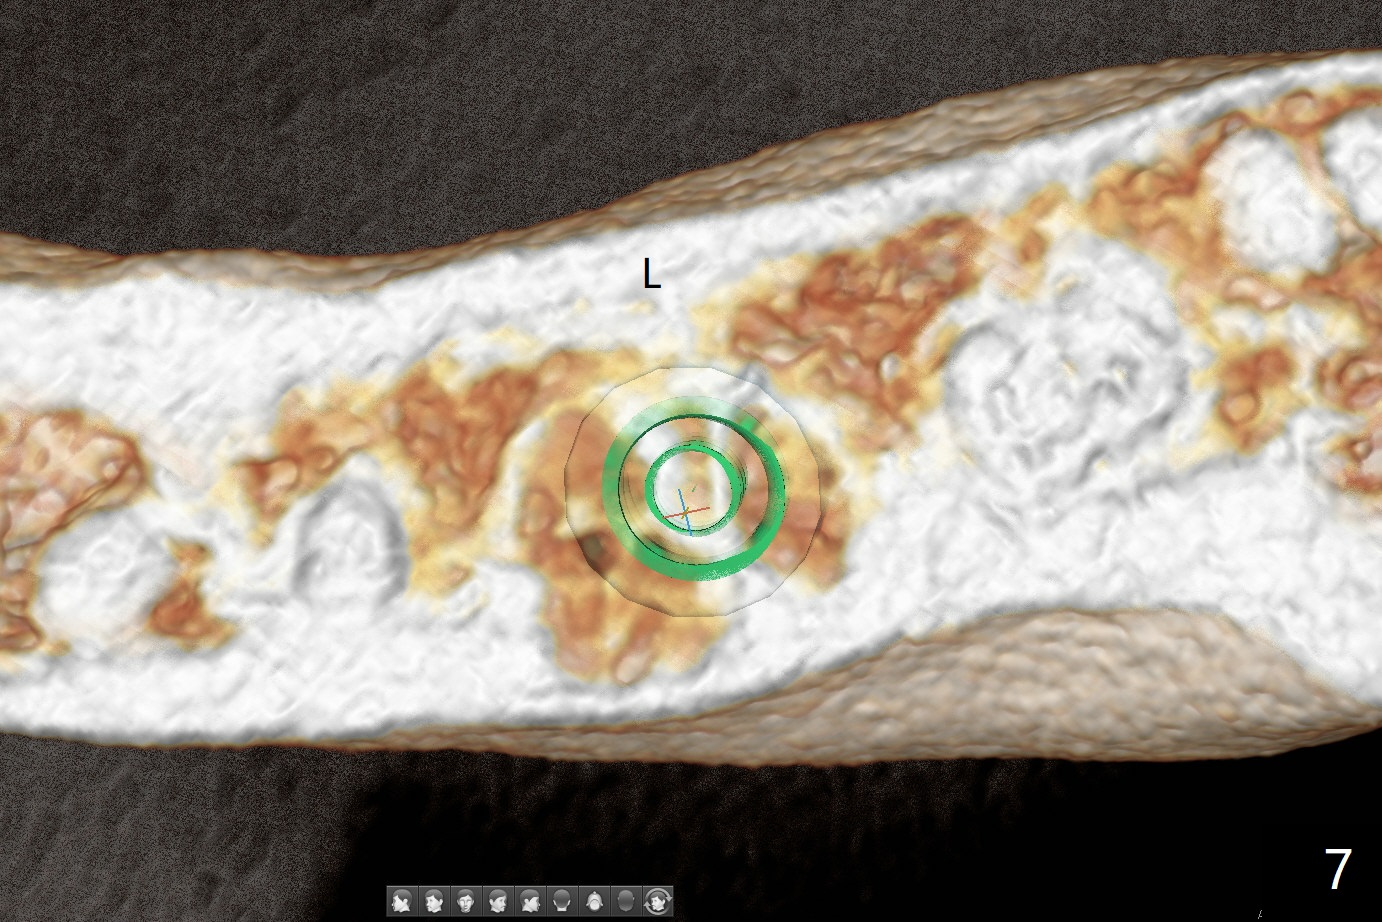

When the patient returns for #15 comp, the bone resorption and swelling at #19 are worse than those 3 years ago (Fig.1,2). After debridement, the mesial socket is large, while the septum is thin, irregular and with undercut (Fig.3). It seems difficult to obtain primary stability for an immediate implant. Vanilla bone and cortical bone hydrated with GEM21 S are placed for socket preservation (Fig.4,5), followed by 12x12 mm BioXclude and 4/0 PGA. In fact the bone height is limited for an immediate implant (Fig.6 (5x10 mm)). There is not enough bone in the septum for primary stability (Fig.7 (cross section of 3D image; L: lingual)). The socket heals 16 days postop (Fig.8). It appears that the granulation tissue is covered by a thin layer of granulation tissue (Fig.9 *), while the membrane remains in place (M). In fact the bone graft remains in the soft tissue zone as well as the hard tissue one (Fig.10). In spite of no apparent loss of bone graft (Fig.4,10), the graft seems to shrink in height 3.5 months postop (Fig.11), while the crest decreases (compare Fig.1 and 11). The keratinized gingiva is wide, but the alveolus reduces in width (Fig.12). The buccal crestal bone is lost 3.5 months postop (Fig.13).